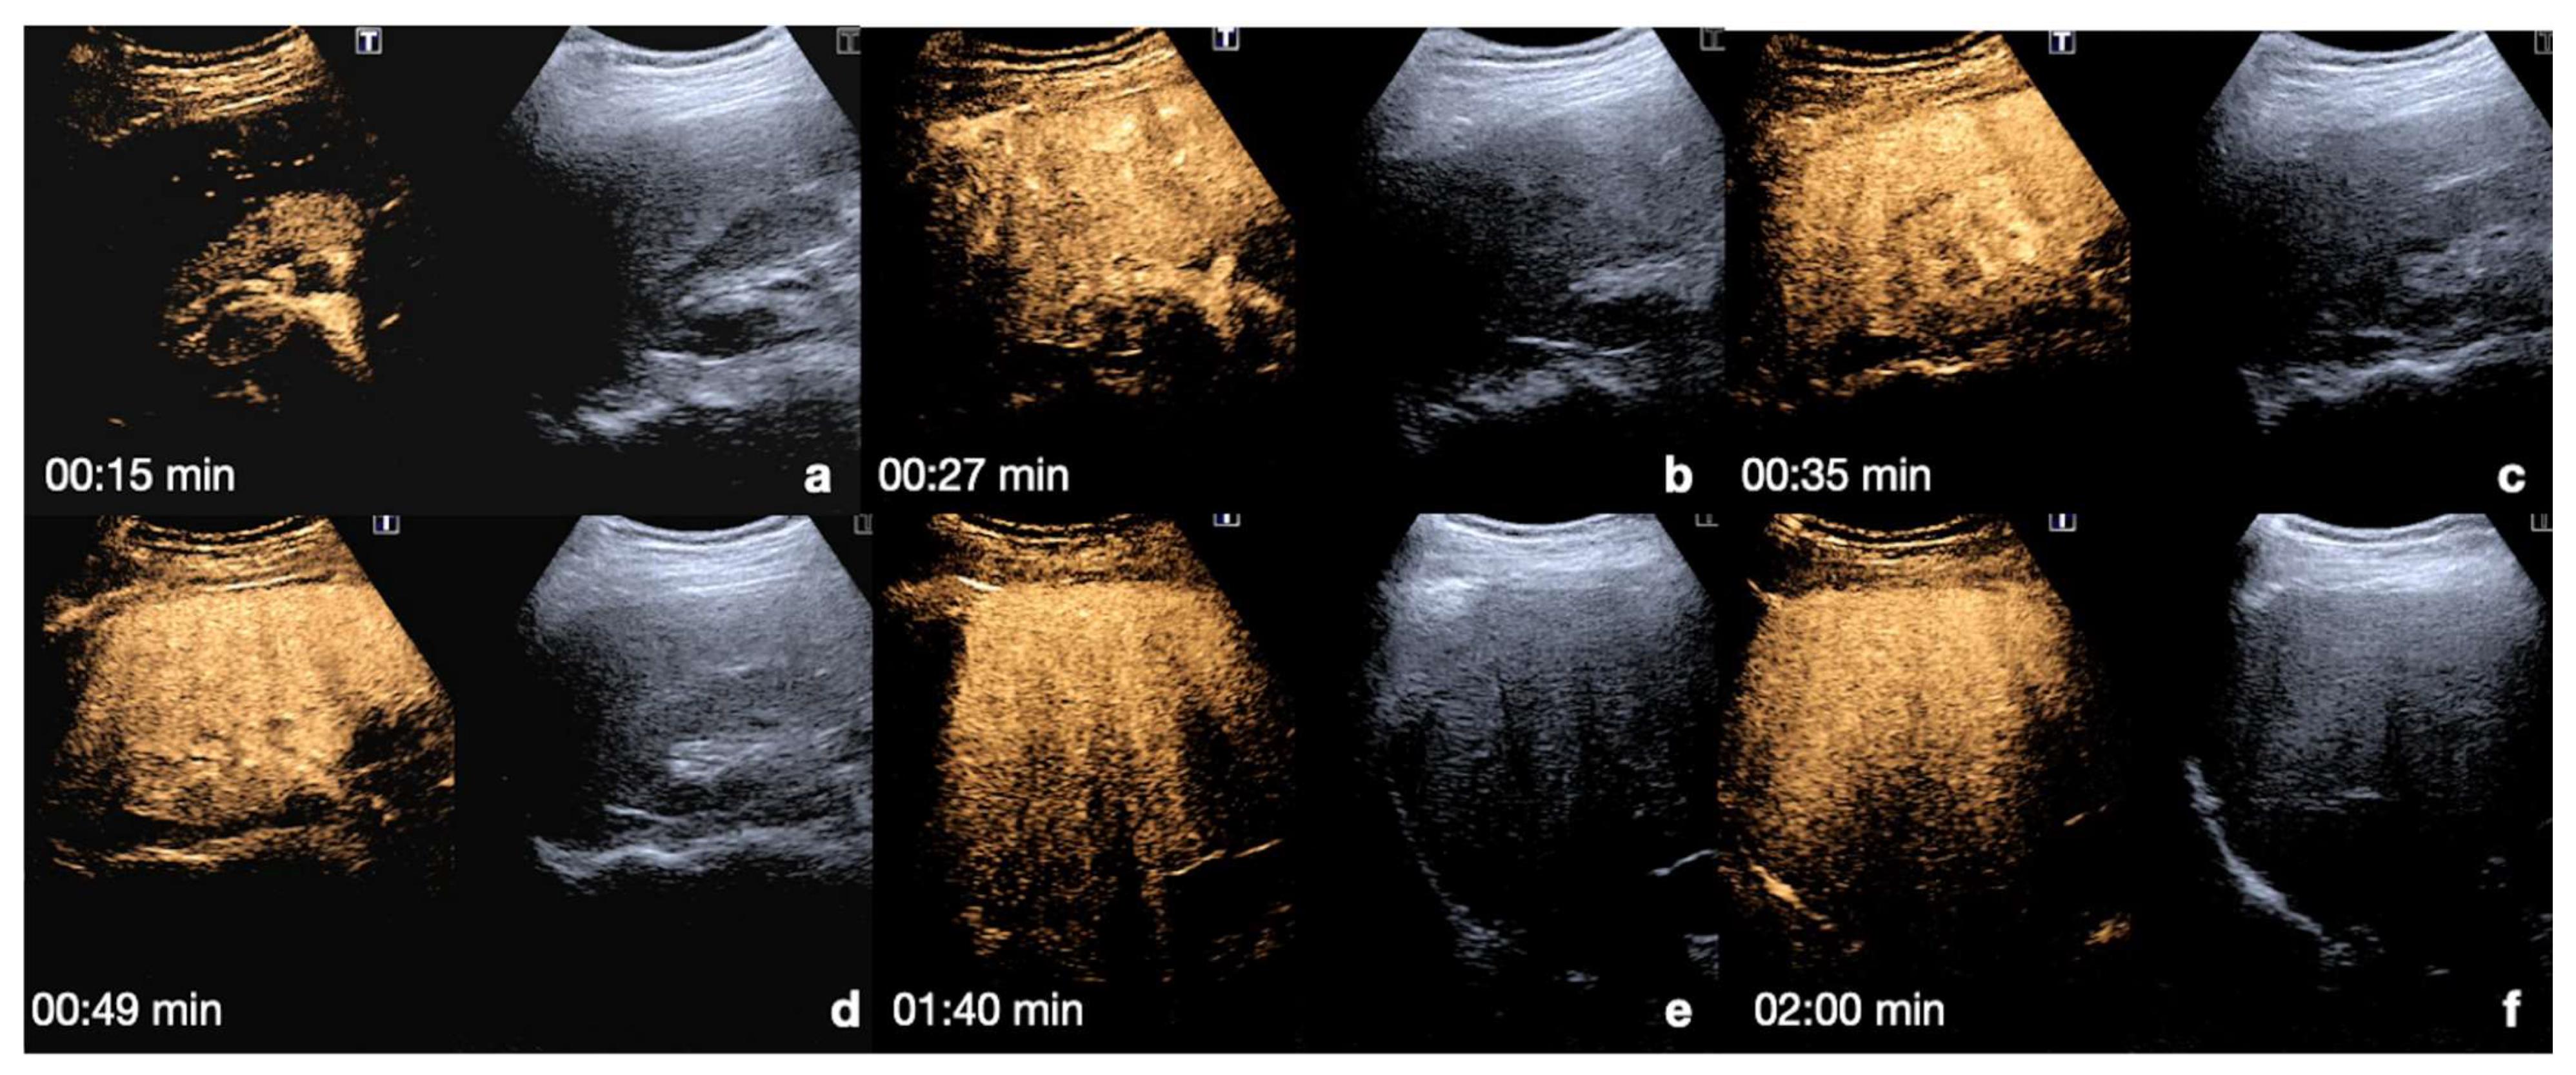

Liver: the arterial phase starts between 10–40 s after the injection. The hepatic and portal phases begin between 40–120 s after the injection, while the sinusoidal phase begins between 120–300 s after. Due to the dual vascular supply in the liver, a homogeneous parenchymal enhancement is shown that is adequate for the detection of organ injury (Figure 5) [13,26,30].

Figure 5.

CEUS findings in a normal liver (a–f). Note the progressive physiological enhancement of the liver in the different phases. Adopted from ref. [30], 2021, Iacobellis, F.; et al.